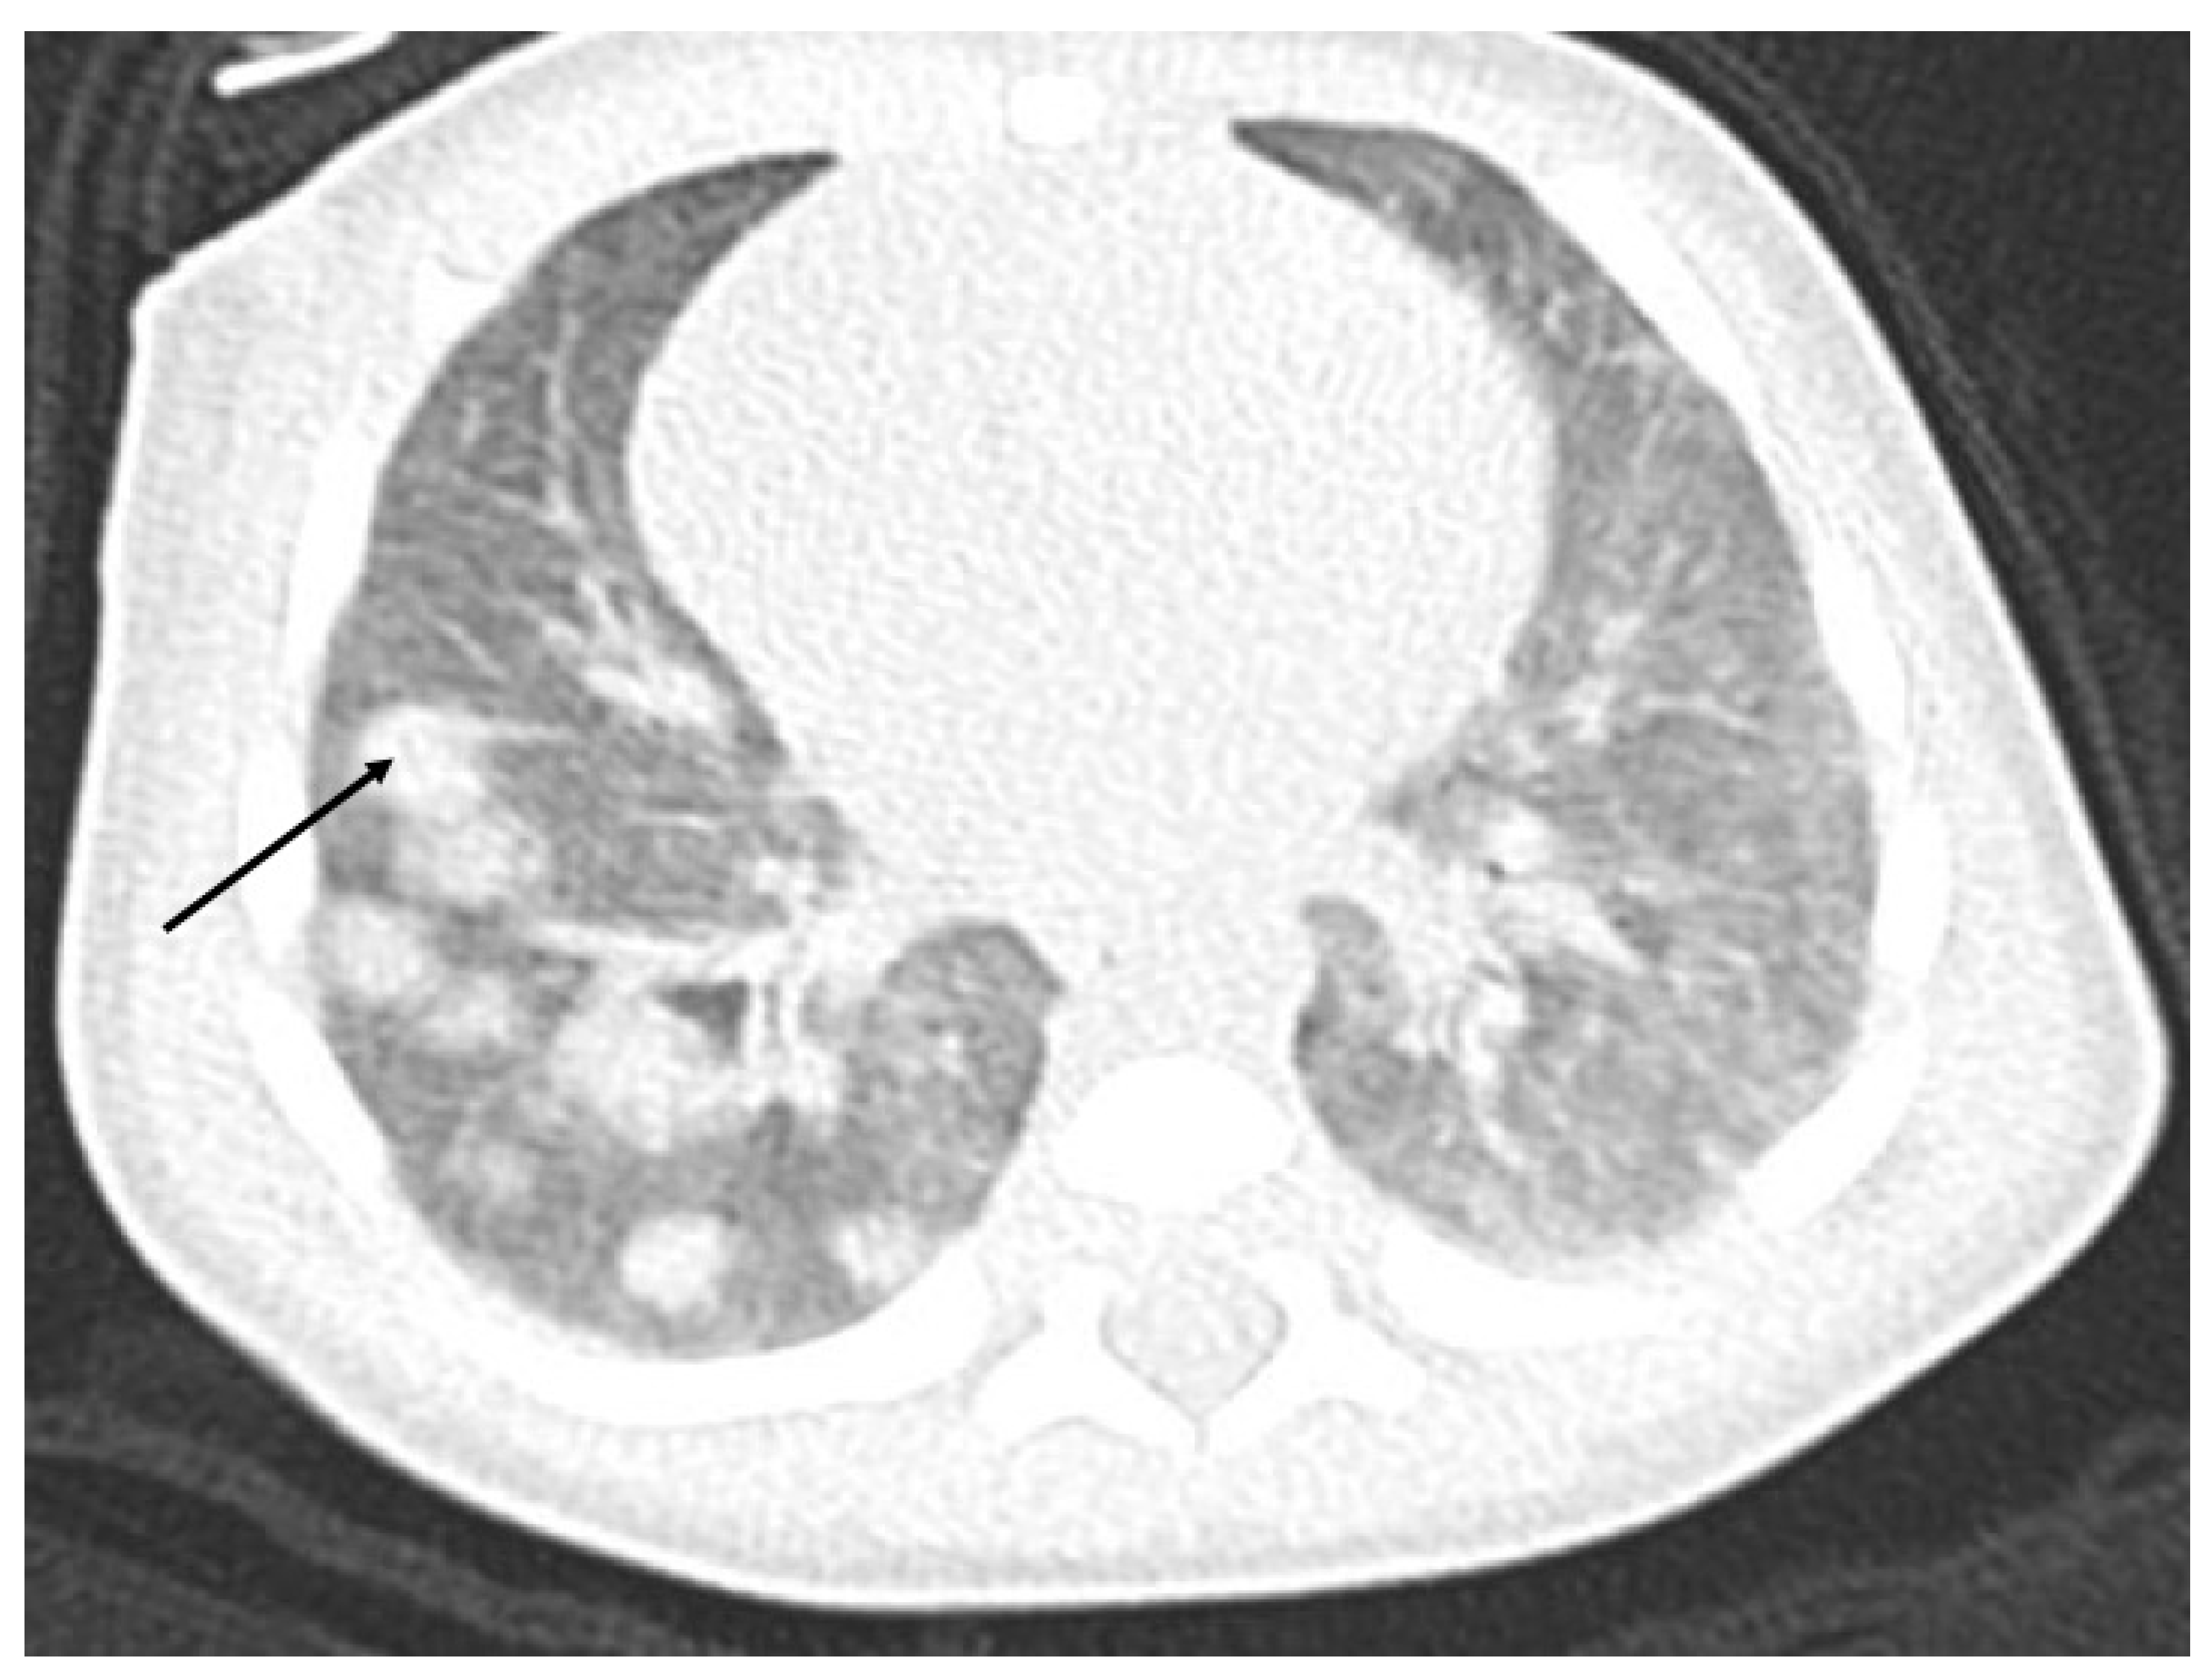

An abdominal nonenhanced (A) and enhanced arterial phase (B) coronal view, arterial phase (C) and portal phase (D) axial view indicate on the hepatic mass with bleeding (A), and central necrosis (Figure 2). After gadolinium contrast injection, there is poor peripheral enhancement in the arterioportal phase (C) and in the late portal venous phase, the CT image shows poor hypodense lesions (D) (Figure 2).

Figure 2. Abdominal CT with liver tumor in the right lobe. An abdominal nonenhanced (A) and enhanced arterial phase (B) coronal view, arterial phase (C) and portal phase (D) axial view indicate on the hepatic mass with bleeding (A), and central necrosis. After gadolinium contrast injection, there is poor peripheral enhancement in the arterioportal phase (C) and in the late portal venous phase CT image shows poor hypodense lesions (D).